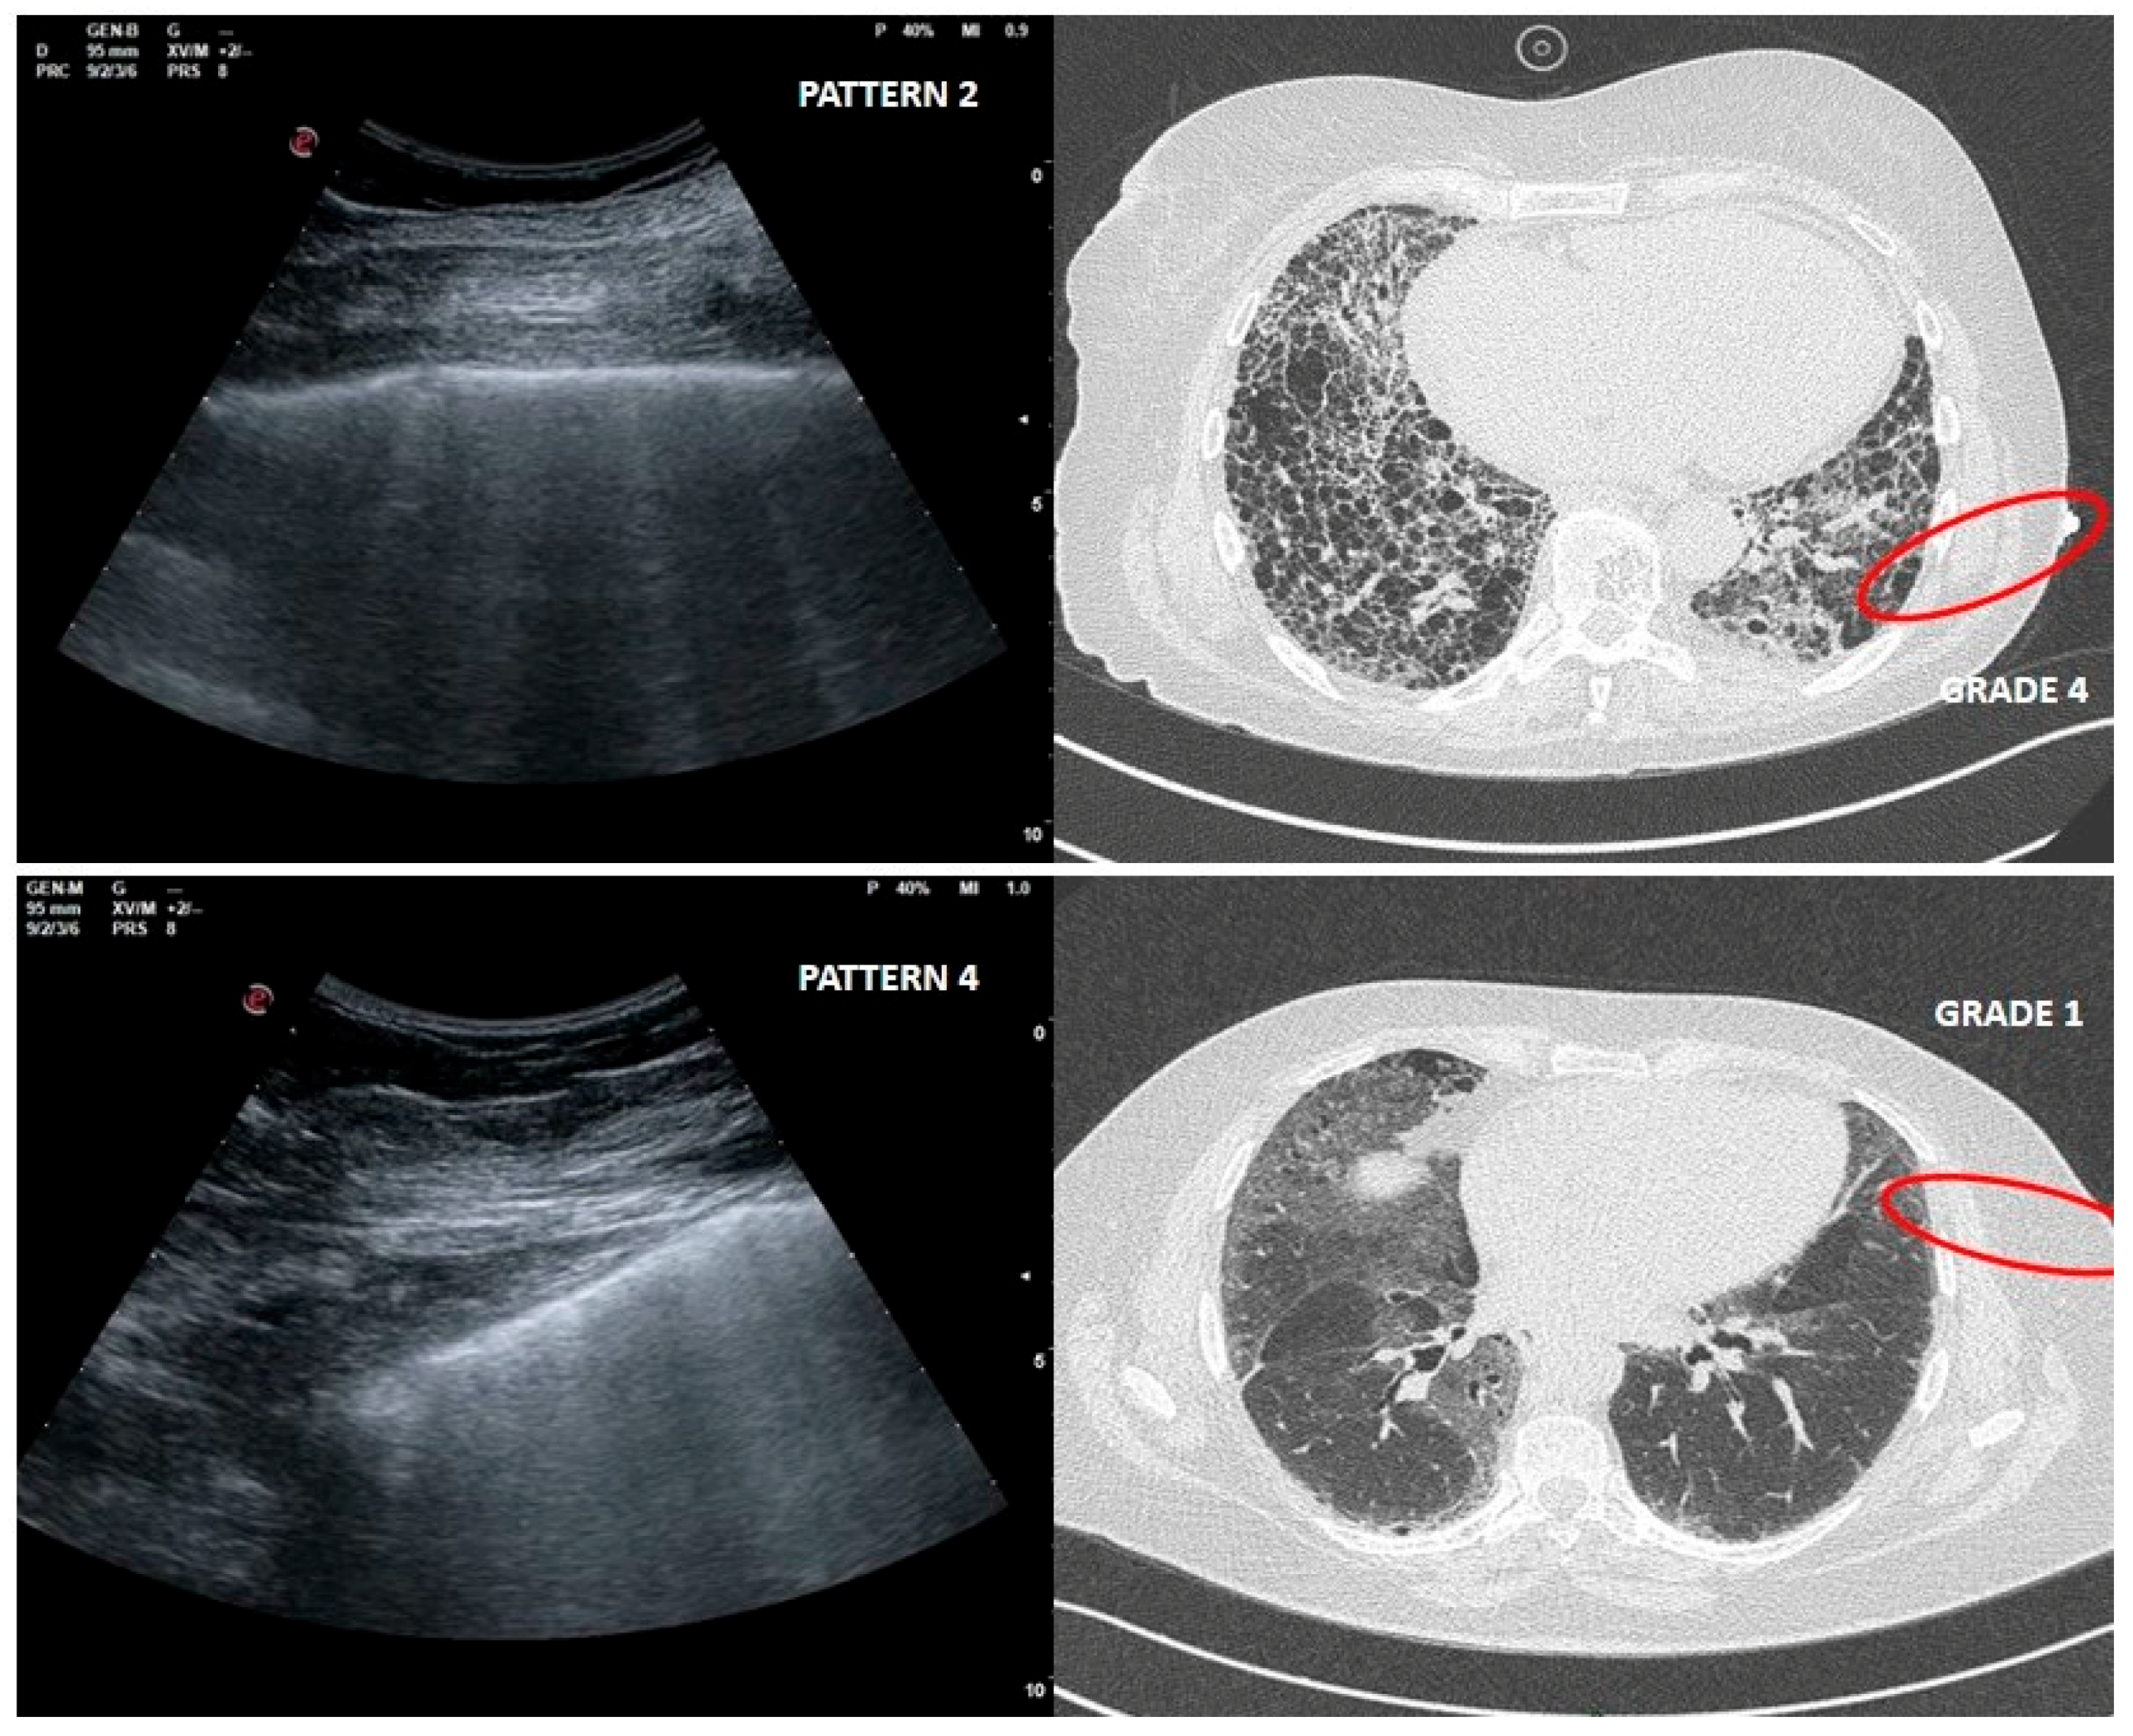

As far as LUS pattern 2 is concerned, agreement with HRCT grade 2 has been reported in 24 out of 30 cases (77%). It is really important to focus on the 4 cases in which a LUS pattern 2 was associated with HRCT grade 4 related to peripheral large honeycomb cysts (massive fibrosis subversion) (Figure 3).

Figure 3.

Upper right and left: large cysts honeycombing and severe fibrotic changes (red circle) with corresponding LUS pattern 2. Bottom right and left: ground glass opacities and moderate fibrotic alterations (red circle) with corresponding LUS pattern 4.

Large cysts honeycomb could represent a limit for LUS, as in this case the air content is greater than in a healthy condition [24].

LUS pattern 4 presented a heterogeneous distribution of corresponding HRCT grades. These could be affected by the low number of cases studied. In five cases out of six, HRCT pattern was however indicative of severe to massive fibrotic changes. Instead, in one case, LUS pattern 4 corresponded to a HRCT grade 1.

This misleading case, in which fibrotic changes were moderate but ground glass opacity (GGO) was reported, corresponded to an early phase of acute exacerbation of IPF (Figure 3).